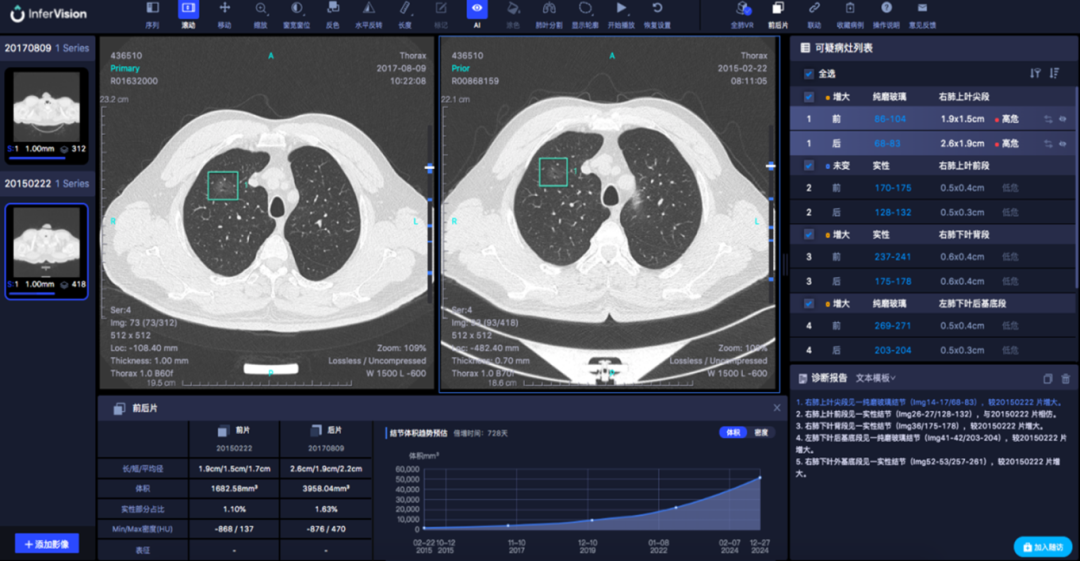

肺癌是发病率和死亡率增长最快 对人群健康和生命威胁最大的恶性肿瘤之一 换言之 发现得越早 治疗效果越好 我们与新华日报交汇点直播平台 江苏省科学传播中心合作 并邀请到了江苏省人民医院(南京医科大学第一附属医院)胸外科主任医师朱全 和我们聊一聊从肺结节到肺癌,如何实现精准诊疗? 专家简介 朱全,主任医师,江苏省人民医院胸外科副主任。中华医学会胸心血管外科学分会胸腔镜学组委员,中华医学会江苏省胸外科分会委员。 01 肺结节的性质 肺结节:< 3厘米 主要是指肺实质内单发或多发直径不超过 3 厘米 的圆形或类圆形结节影。不伴肺不张、肺钙化、肺门淋巴结肿大或胸膜渗出。 结节: <8毫米时称作亚厘米结节 <4毫米称作微结节 肿块: ≥ 3厘米 02 肺结节的分类 (1)实性结节 (2)半实性结节 (纯磨玻璃结节、混合磨玻璃结节) 实性结节 混合磨玻璃结节 结节分类 磨玻璃样结节 03 肺结节≠肺癌 •实性结节恶性率仅7% •部分实性结节恶性率为63% •纯磨玻璃结节恶性率为18% •>20 毫米的结节恶性率有80% 肺磨玻璃肺结节的演变 01胸部X光平片 对肺癌的漏诊率30% 不能发现肺小结节 02 薄层CT 5mm层厚已成为历史---导致误诊! 薄层CT比常规CT提供了7-10倍信息 (普通CT 60张对比 薄层CT 360-600张) 03 正确使用PET/CT • 能够评估结节的代谢活性。 • 对大于1厘米的实性结节有意义 • 对纯磨玻璃和混合性磨玻璃结节无效 • 不易区分炎症和结核 强调!!! 磨玻璃结节要经过随访 2-3个月的随访很重要 炎症的比例10% 随着时间会消失 肺结节CT影像AI辅助检测 外科手术的微创化 切口的微创化 全胸腔镜→3孔→2孔→单孔 肺切除范围的变化 非解剖性肺切除:楔形 解剖性肺切除:全肺切除、肺叶切除、肺段切除术、肺亚段切除术、肺次亚段切除术 肺段切除 早期肺癌的微创治疗外科手术的精准化 早期肺癌外科治疗中的规则: 保证肿瘤学效果是首要任务保留更多有功能的肺组织 三维CT支气管血管成像(3D-CTBA)肺结节与早期肺癌